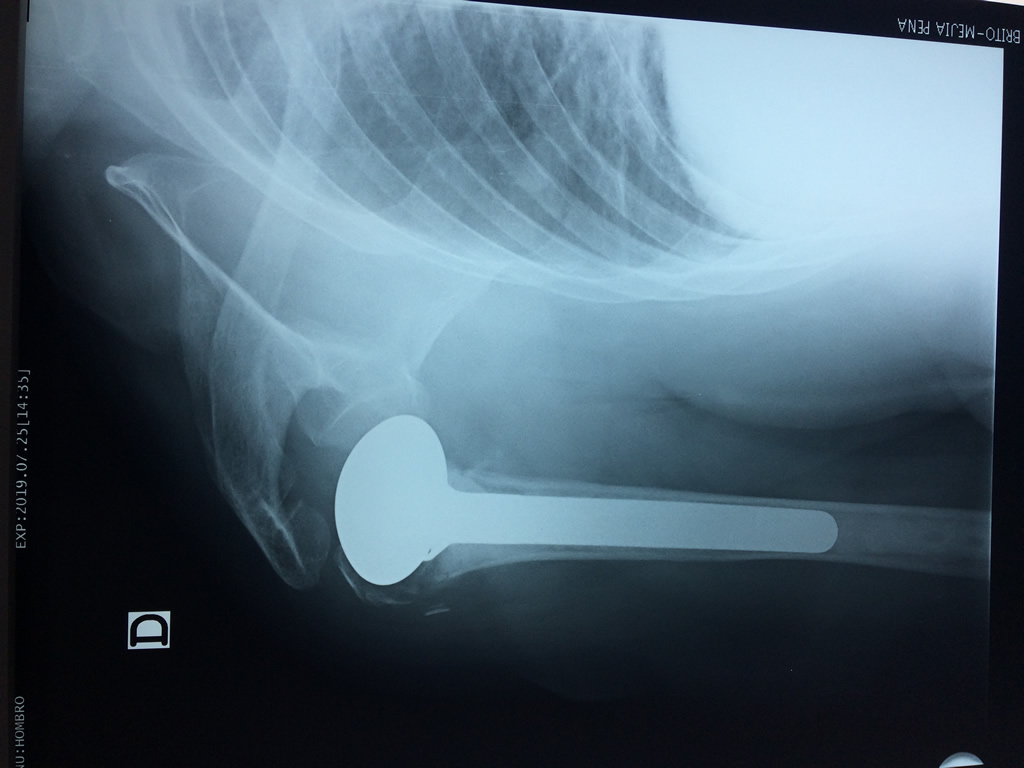

En anatomía humana, el hombro es la parte del cuerpo donde se une el brazo con el tronco. Está formado por la conjunción de los extremos de tres huesos: la clavícula, la escápula y el húmero; así como por músculos, ligamentos y tendones.

La principal articulación del hombro es la que une la cabeza del húmero con la escápula, recibe el nombre de articulación escapulohumeral y presenta dos superficies articulares, una de ellas corresponde a la cabeza del humero que tiene forma semiesférica y la otra es la cavidad glenoidea de la escápula, estas superficies están recubiertos por cartílago que permiten un movimiento suave e indoloro.

Exteriormente una envoltura de tejido blando circunda el conjunto, es la llamada cápsula articular que está reforzada por varios ligamentos que le dan estabilidad e impiden que los huesos se desplacen más allá de sus límites fisiológicos. Un conjunto de músculos y sus tendones se unen a las superficies de los huesos y hacen posible la movilidad de la articulación, entre ellos es muy importante el manguito rotador formado por cuatro músculos que proporcionan movilidad y estabilidad al hombro.

Varias estructuras transparentes en forma de saco llamadas bolsas serosas, permiten el deslizamiento suave de los diferentes componentes móviles. El hombro es la articulación con mayor amplitud de movimientos del cuerpo humano.